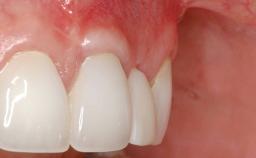

Treatment of Soft-Tissue Fenestration in the Esthetic Zone

This case demonstrates that a connective-tissue graft in combination with a coronally positioned graft is an effective method of treating cases with peri-implant mucositis and an abutment-level sinus abscess. A 42-year-old man presented with a swelling adjacent to an implant crown at site 21. The swelling had been present for approximately three weeks and was constrained to the buccal and palatal gingival aspects of the implant. A discharge was noted on finger pressure, with localized gingival recession present on the mid- and distolabial aspects of the crown.